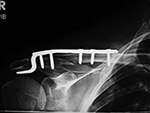

The clavicle hook plate is a clavicular plate with a hook engaging below the acromion (figure: clavicle hook plate). It is intended for fixation of both lateral clavicle fractures and acromioclavicular joint injuries (Synthes). The plates are precontoured as left and right plates and are available with 6 or 8 holes, one of which is an anterolateral screw hole for additional options for screw fixation in the lateral clavicle. The dynamic compression screw holes accept 3.5 mm cortex or 4.0 mm cancellous bone screws. The offset hook design is intentional to avoid insertion of the hook into the acromioclavicular ligament. The plate achieves a high percentage of bony unions and a low percentage of complications, but there are concerns about possible long-term complications involving the acromioclavicular joint (Tiren, 2012; Gaetke-Udager, 2019). A similar hook design is sometimes used in other locations, such as with distal ulnar fractures (figure: distal ulnar hook locking compression plate).

Clavicle hook plate |